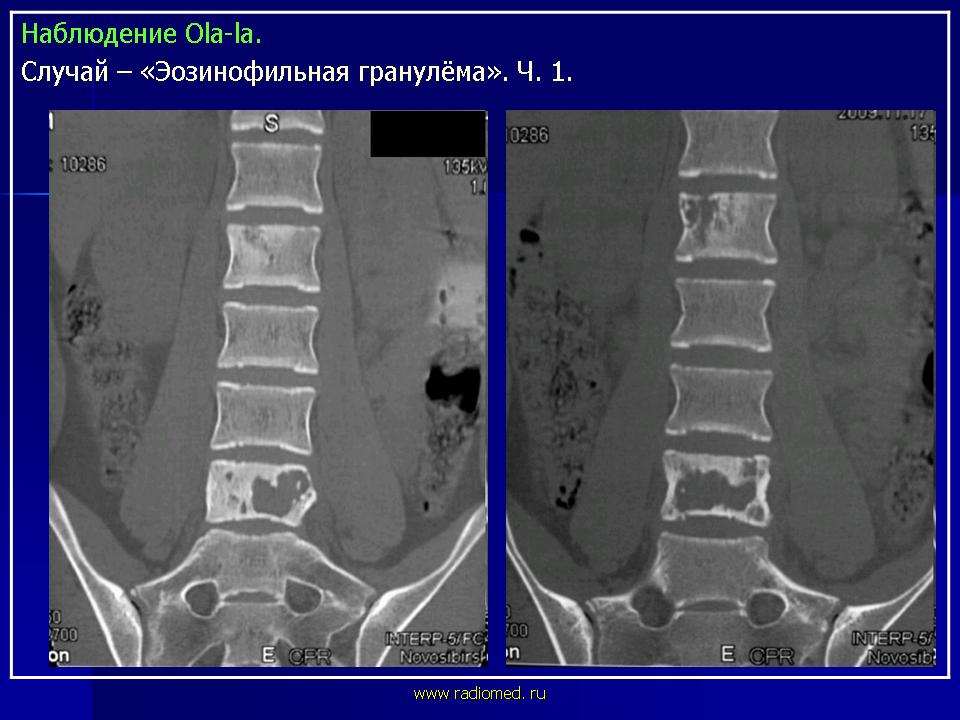

Продолжение.

Тело позвонка является наиболее часто поражающейся частью позвоночника. Ранние поражения проявляются, как литические очаги.

Формируется «VERTEBRA PLANA», что может привести к боли и значительным неврологическим расстройствам.

LCH у 17-летней девочки с болями в спине.

На КТ изображении визуализируется неправильной формы литическая деструкция тела позвонка (стрелка).